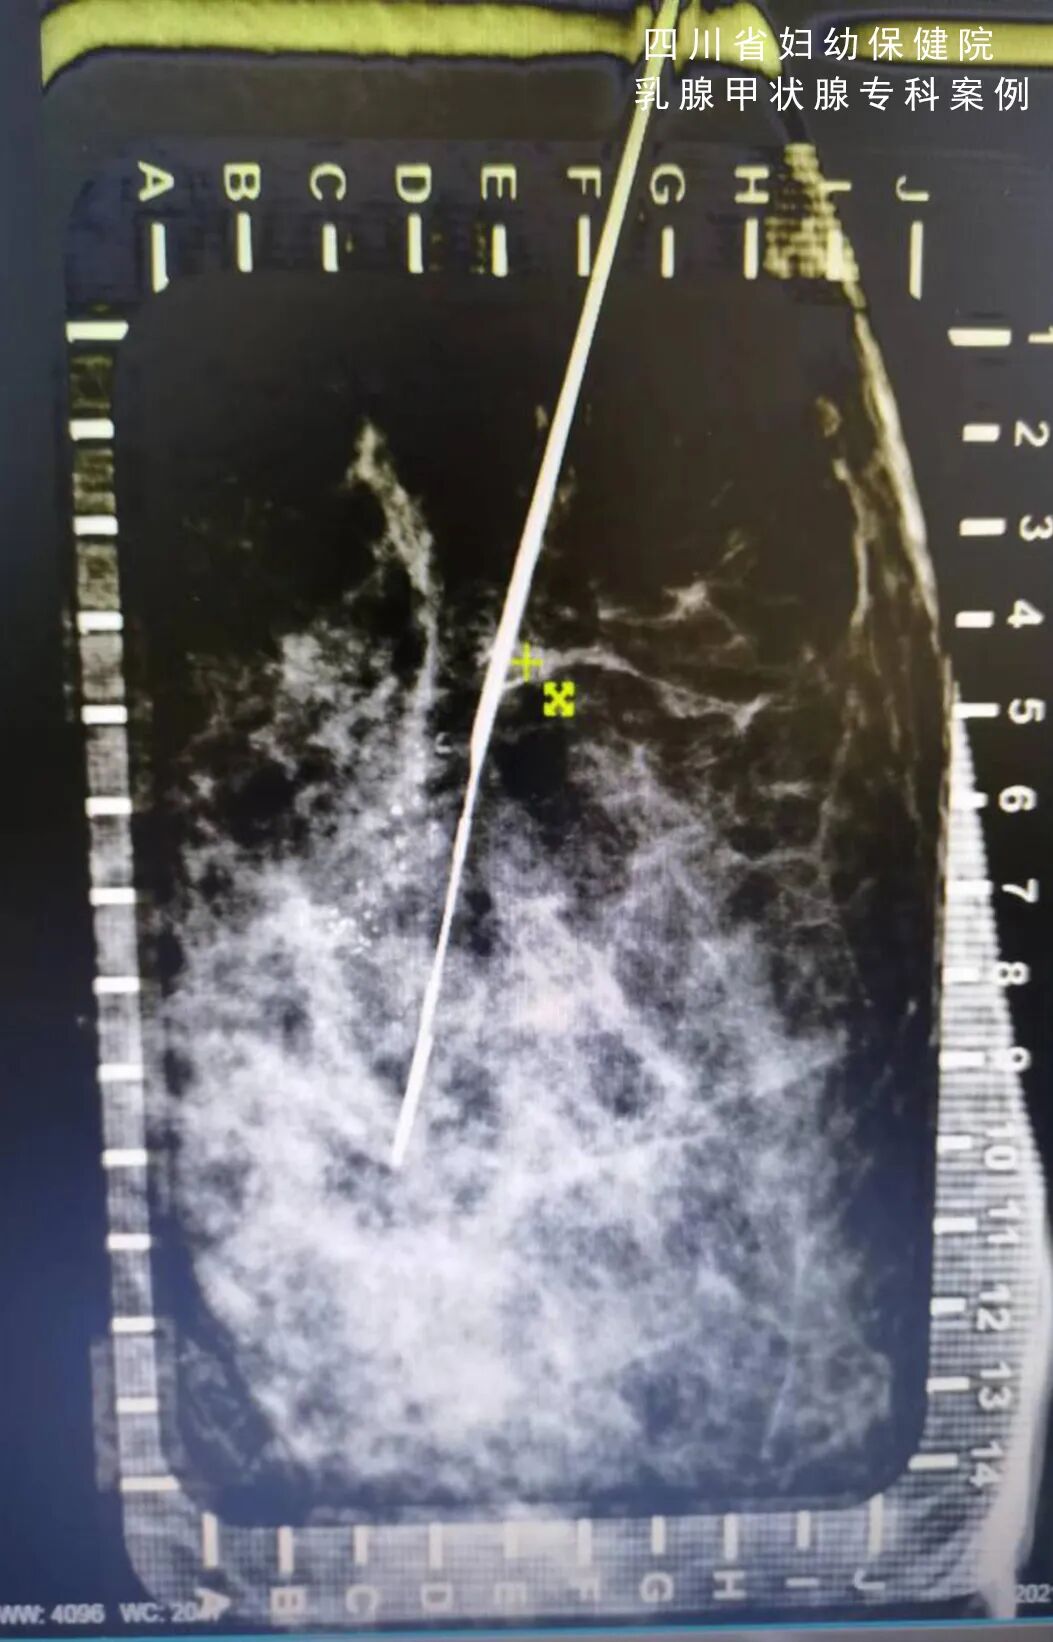

大致过程是,在其中一种体位下,将一次性的无菌定位钩针垂直插入病灶处。再变换体位,确定在另外一个平面上是不是也在病灶里。

通过两个平面的确认,保证三维立体定位的精准。手术中,临床医生通过寻找定位钩针,沿着钩针附近切除,可以在保证切除病灶的同时,减小切除范围。

怎么制造手术钩针看医生如何精准“钩出”乳腺钙化灶,将早期乳腺癌“绳之以法”_https://www.jmylbn.com_新闻资讯_第4张

(在头尾位上复核确定位置)